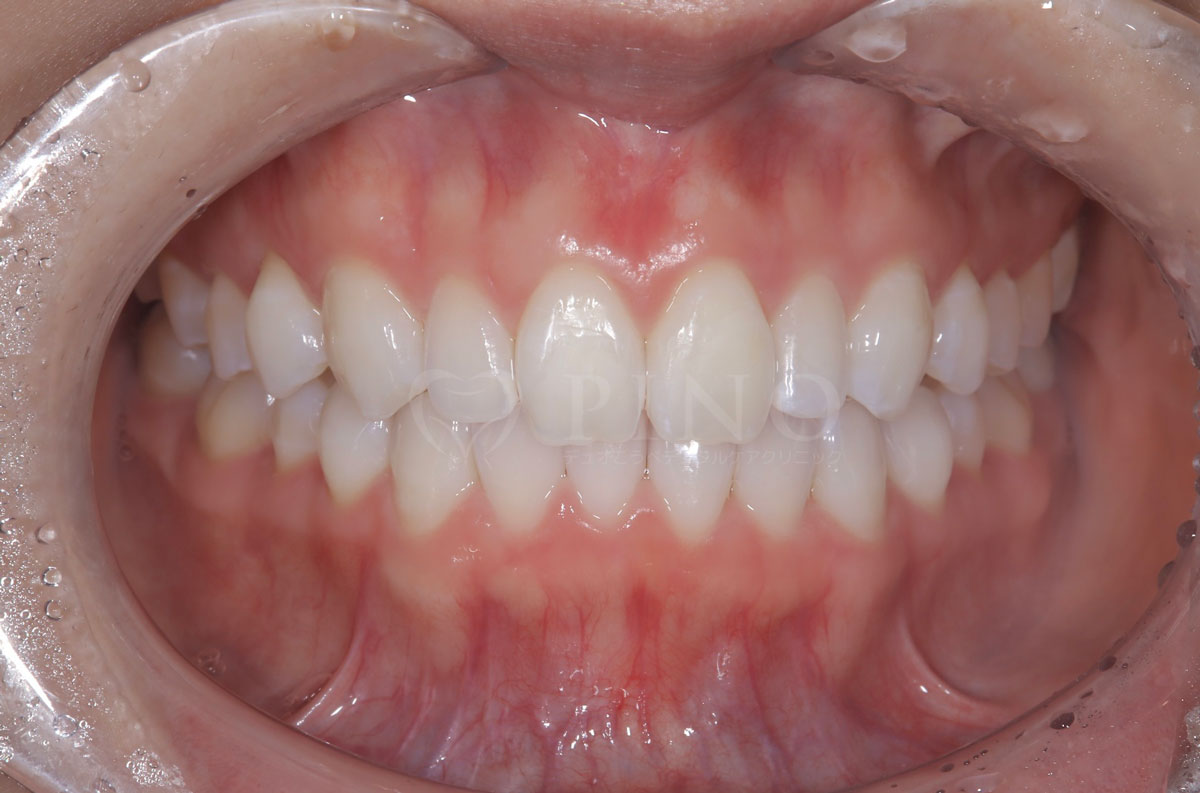

症例8:歯が全体的にガタガタして気になる(30代女性)

主訴 歯が全体的にガタガタして気になる 診断名 上下顎1級叢生 治療方法 マウスピース全顎矯正 抜歯 あり 上2本 オルソパルス あり 治療期間 1年5ヶ月 費用 891,000円+補綴治療費(セラミック320,000円) 副作用・注意点 歯を抜く際に痛みを伴う可能性がある、矯正後後戻りを防ぐためリテーナーの使用が必要となる -